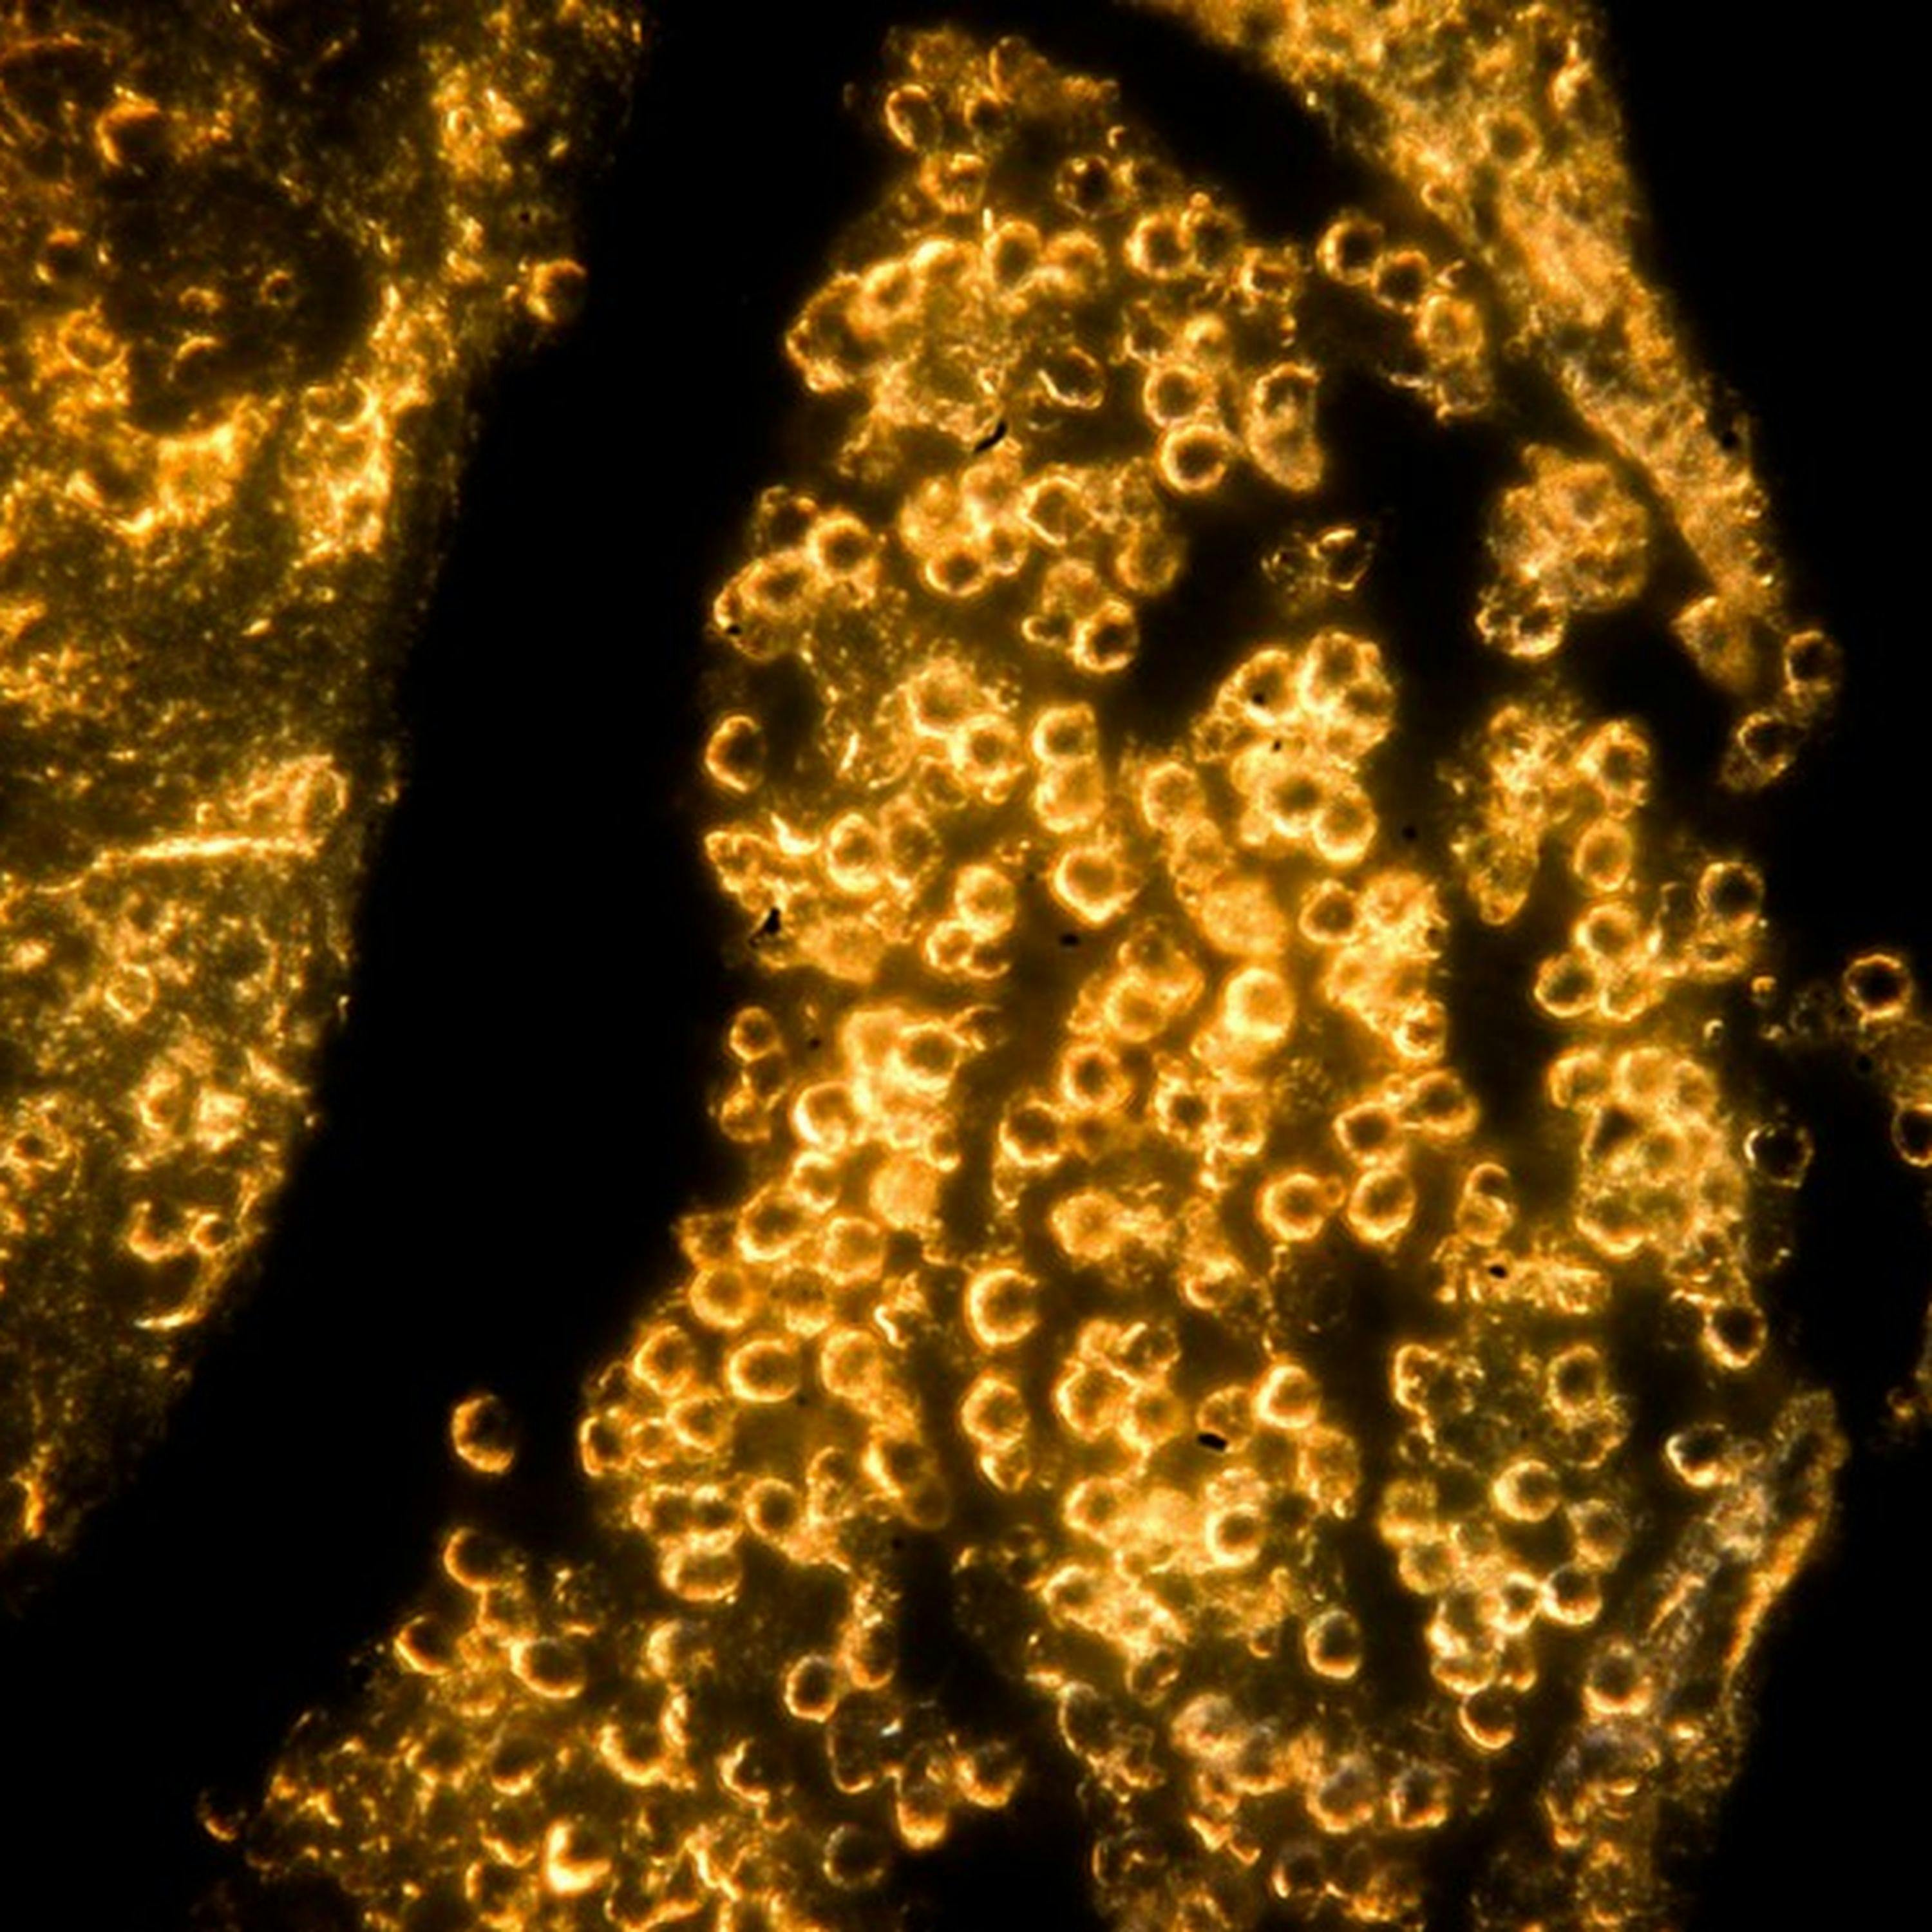

b'Veterinarians are using gold nanoparticles to control the growth of cancerous tumors. Our GDPR privacy policy was updated on August 8, 2022. Visit acast.com/privacy for more information.\\nLearn more about your ad choices. Visit megaphone.fm/adchoices'